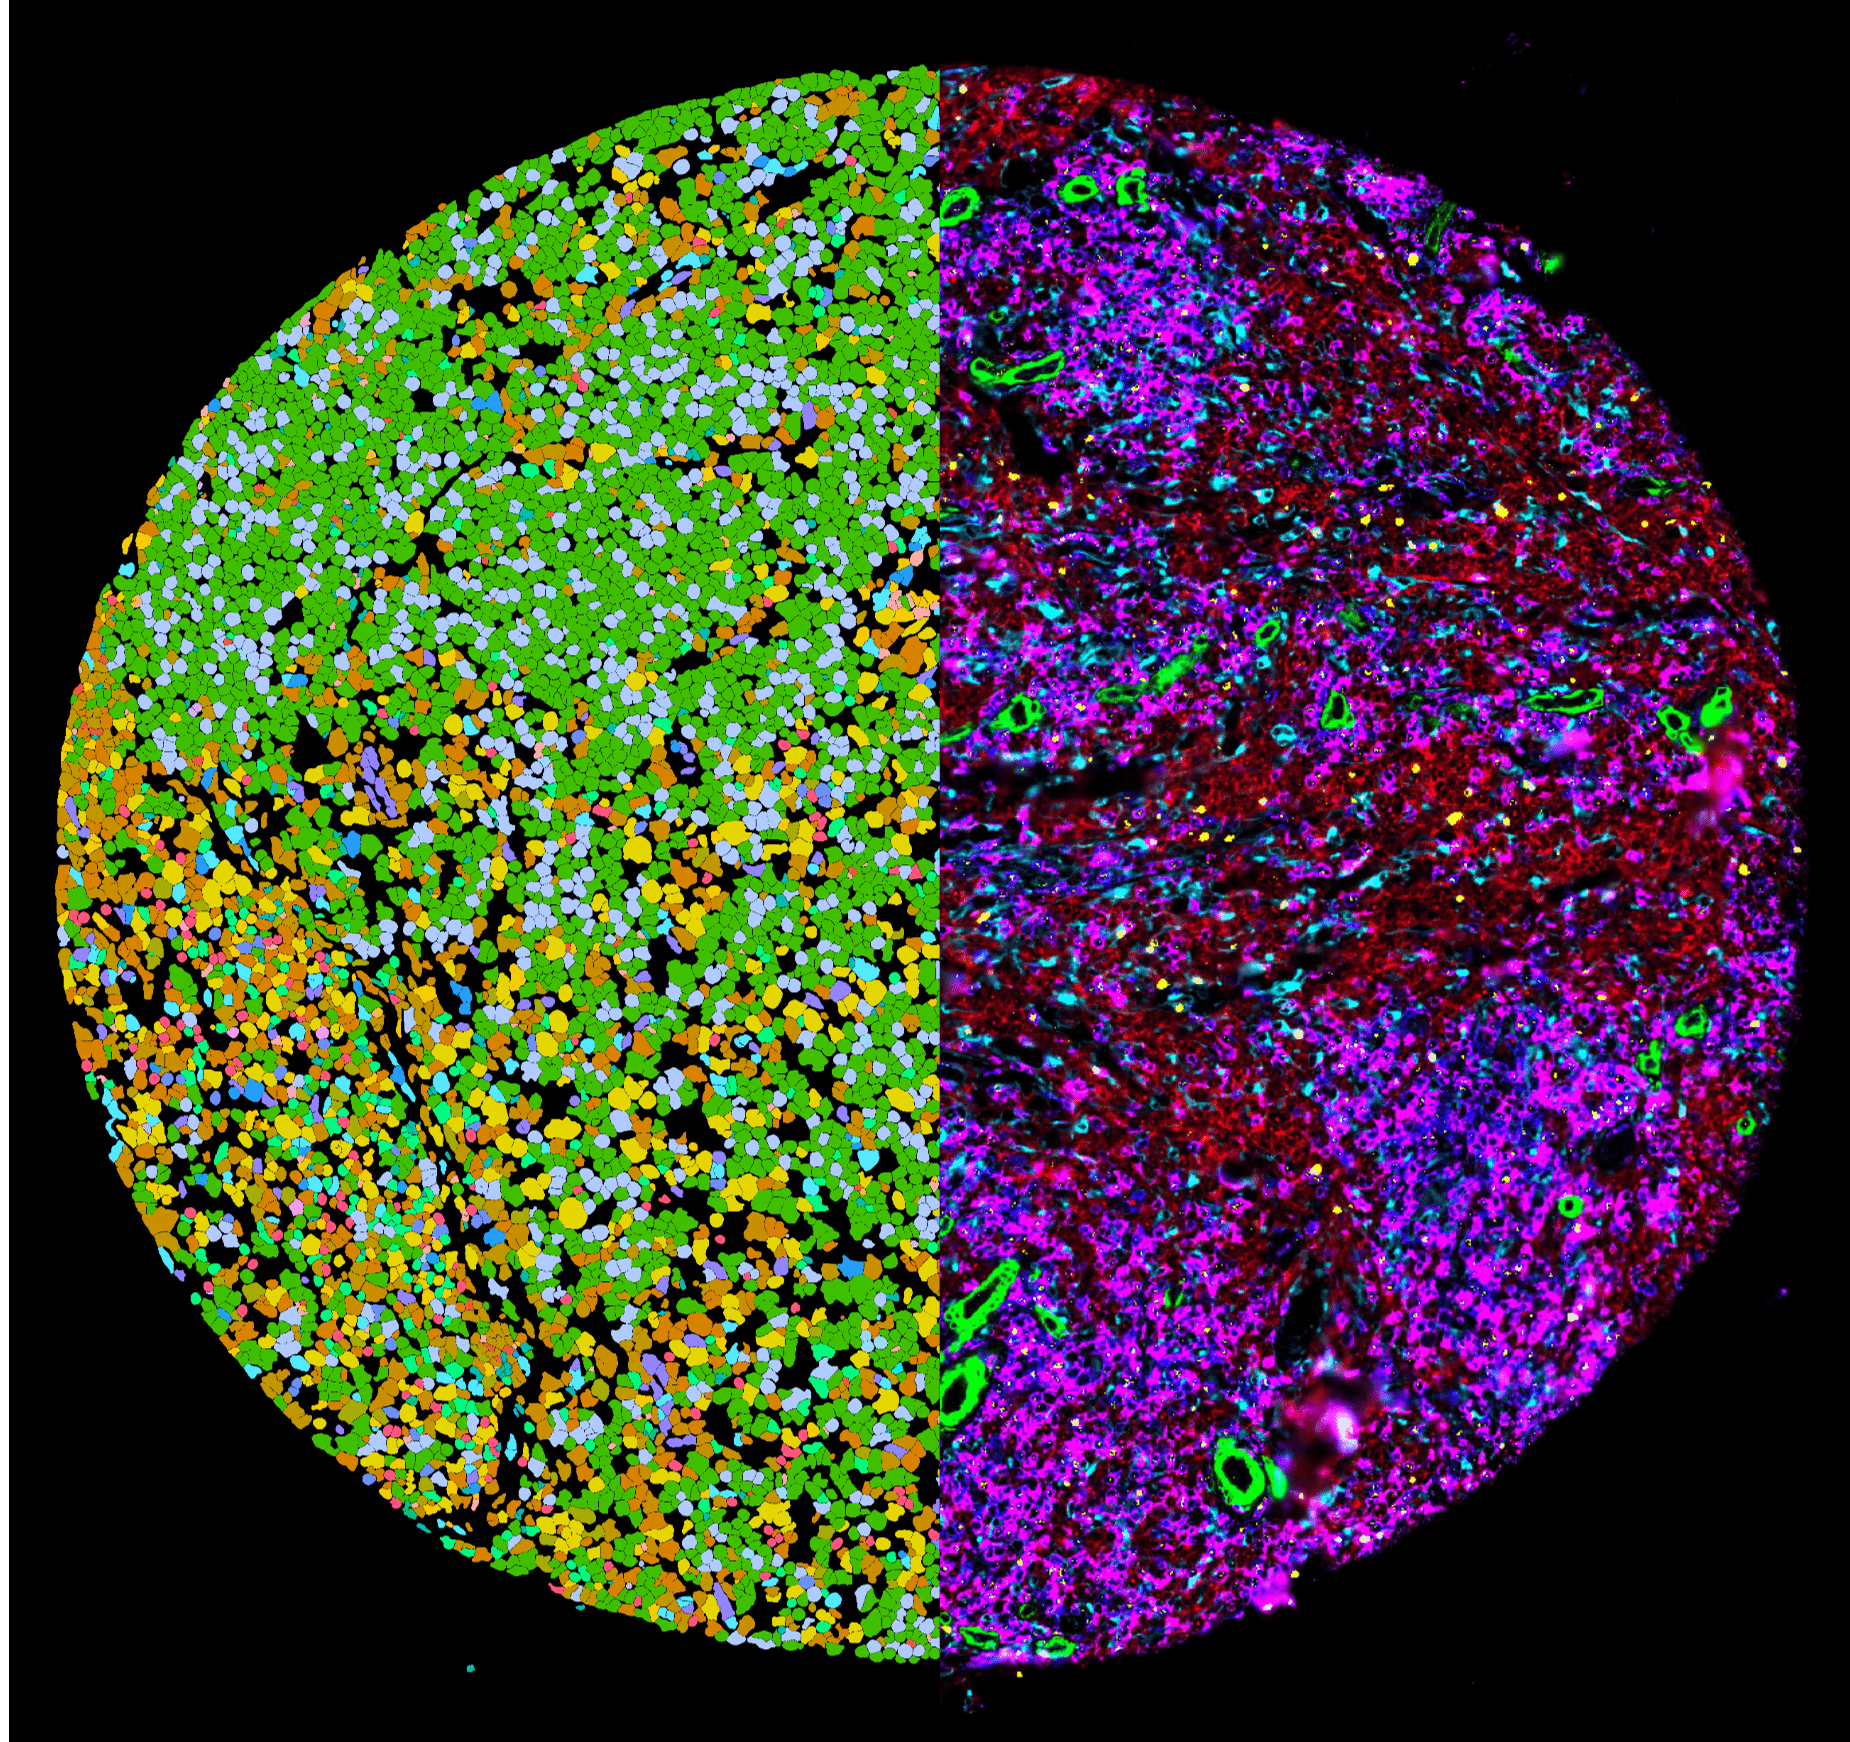

IMMUNO-CAR ZURICH

Innovative Zelltherapien für eine gezielte Krebsbehandlung

CCCZ Leuchtturmprojekt